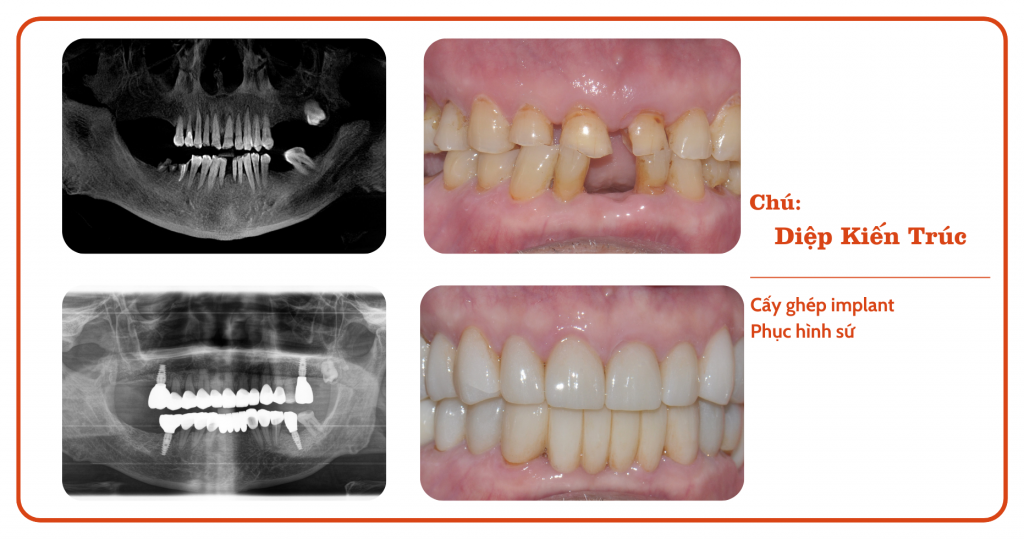

“Từ ngày mất răng chú chẳng thiết tha gì đến chuyện ăn uống, cười nói nữa, cứ nhai qua loa rồi nuốt vội thôi, chẳng còn thấy ngon miệng gì” – Đó là nỗi niềm của chú Diệp Kiến Trúc suốt gần 5 năm trời. Chỉ đến khi quyết định trồng răng Implant, chú mới thực sự cảm nhận được những thay đổi tích cực, không chỉ về sức khỏe mà còn cả về mặt thẩm mỹ.

Sau khi trồng răng Implant tại Chez, chú Diệp đã có thể ăn uống thoải mái, cười nói tự tin hơn. Chú vô cùng hạnh phúc và không quên gửi lời cảm ơn đến toàn bộ đội ngũ Nha Khoa Chez.